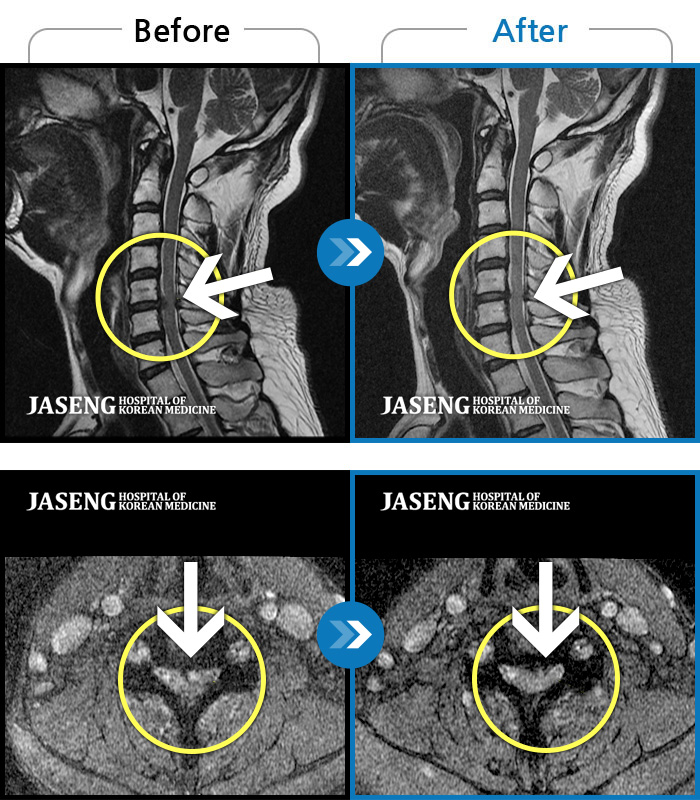

ȯںп Ǹ ǿ ԿǾ, ο ġ ۿ Ƿ ġḦ Ͻñ ٶϴ.